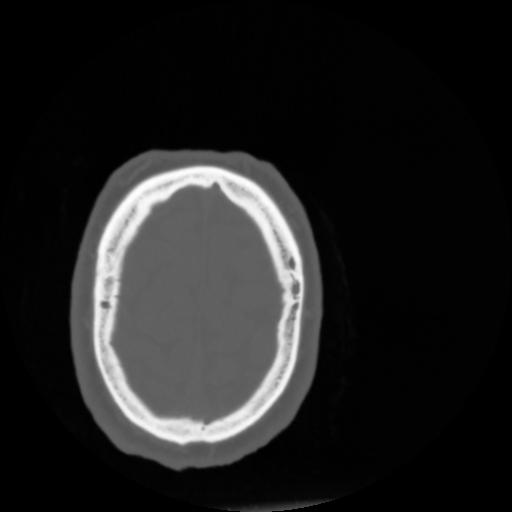

4 CEREBRO,,Vol,0.5,CEREBRO,,